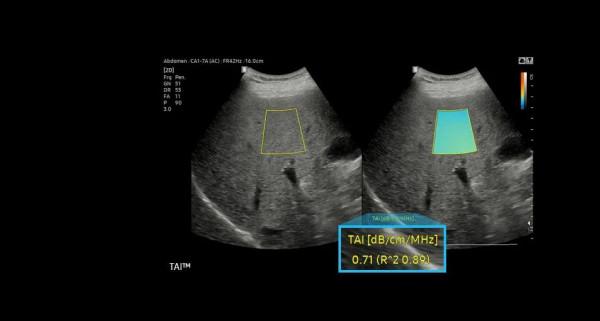

RS85 Prestige搭載了多款智慧應用,幫助臨床醫護人員做出更可靠的評估。如能夠提供HRI比率的EzHRI系統;S-Detect for Breast系統則能夠為乳腺超聲檢查提供標準化報告,並最佳化工作流;利用定量組織衰減測量來評估脂肪變性肝臟變化的TAI系統等。